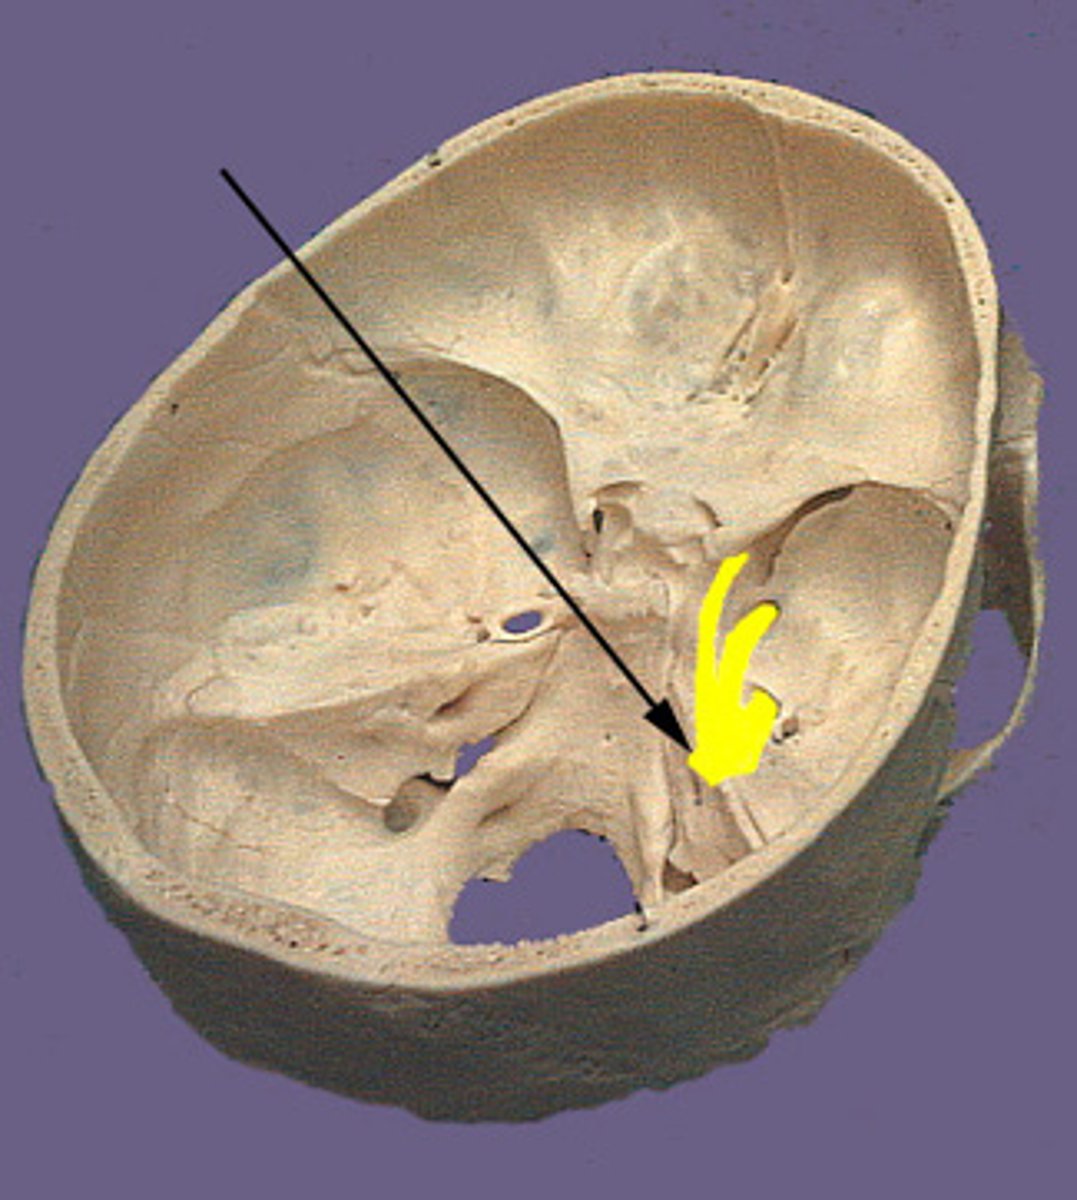

anterior cranial fossa